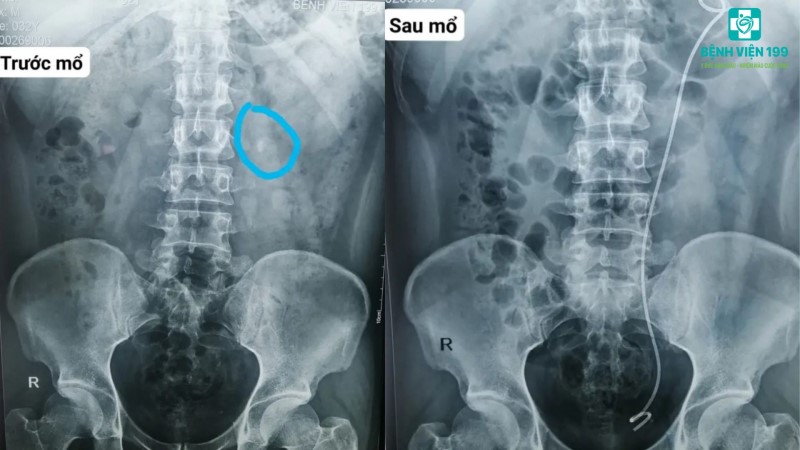

TIN TỨC BỆNH VIỆNPhẫu thuật nội soi lấy sỏi niệu quản cho cụ ông 85 tuổi

Sáng 26.8, Bệnh viện 199 Bộ Công an (tại Đà Nẵng) cho biết vừa phẫu thuật nội soi sau phúc mạc lấy sỏi niệu quản thành công cho cụ ông 85 tuổi.